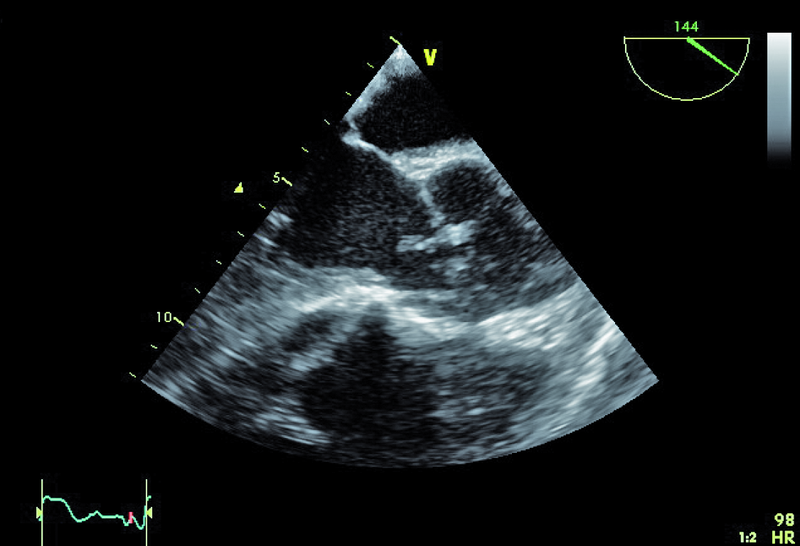

3. Dodatkowe echo w drodze odpływu lewej komory (ryc. 2, 3) – wegetacja?

5. Perforacja lewego płatka (płatków?) zastawki aortalnej (ryc. 3).